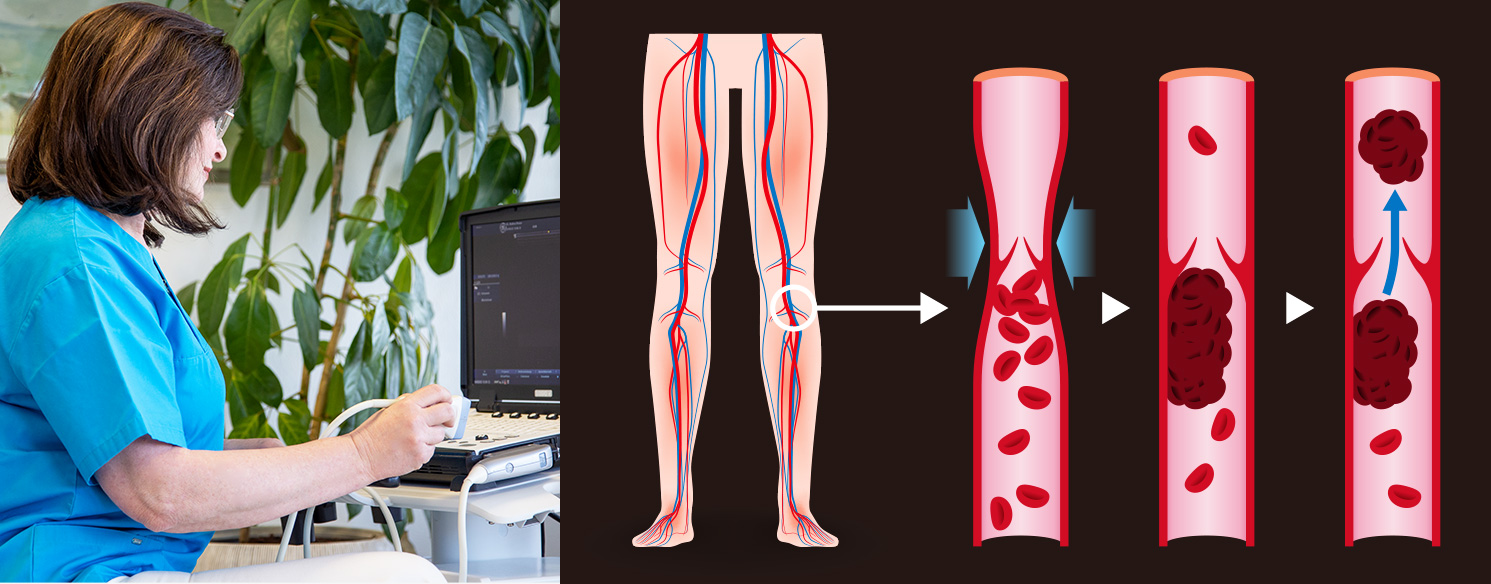

Thrombose

Unter Thrombose versteht man einen Verschluss einer Vene aufgrund eines Blutgerinnsels. Man unterscheidet die oberflächlichen und die tiefen Venenthrombosen, wobei die Oberflächlichen auch als Venenentzündung (Thrombophlebitis) allgemein bekannt sind. Hierbei entstehen im Bereich einer Krampfader Verhärtungen mit Umgebungsrötung und Überwärmung sowie erheblichem örtlich begrenztem Druckschmerz. Eine tiefe Venenthrombose ist wesentlich gefährlicher, sie ist der Verschluss einer tiefen Vene und führt nicht selten zu Embolien – Abschwemmung von Teilen des Blutgerinnsels in andere Körperregionen – am häufigsten in die Lunge. Diese tiefen Venenthrombosen können spontan auftreten, häufiger jedoch im Zusammenhang mit Operation oder Funktionseinschränkungen der Beine (z. B. Verletzungen, Knochenbrüche usw.). Die Patienten bemerken heftige Schmerzen und Schwellung der betroffenen Extremität. Ein sofortiger Arztbesuch ist erforderlich, um mittels Laboruntersuchung und Duplexsonografie die Thrombose bestätigen oder ausschliessen zu lassen. Die Behandlung erfolgt in den meisten Fällen ambulant mit einem Medikament zur Hemmung der Blutgerinnung („Blutverdünnung“) und einem Kompressionsstrumpf. Die Behandlungsdauer und das Behandlungskonzept müssen individuell festgelegt werden.